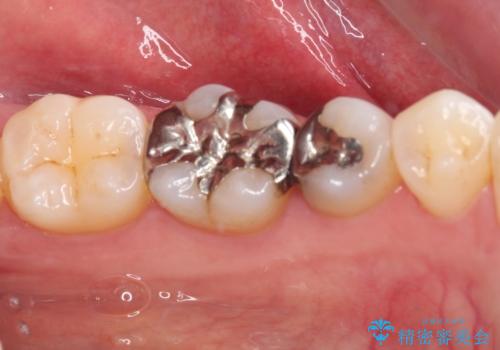

- 銀歯をセラミックにしたいとのことで来院された患者様です。

まず麻酔をして銀歯を外し、むし歯を除去し、形を整えて型取りします。

銀歯をセラミックにしたい セラミックインレー修復